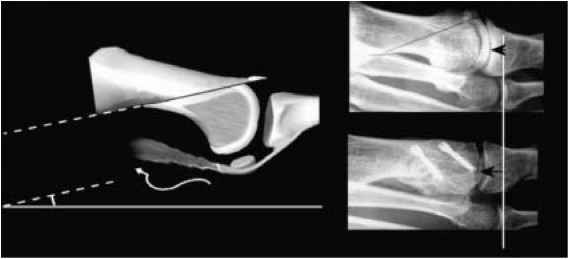

Osteotomy of the proximal phalanx (big toe)

A wedge of bone is removed from the proximal phalanx (bone at the base of the big toe) and gap closed and held with a screw or wire. The procedure elevates the big toe allowing the individual to rock of the toe, this can help reduce pain when walking.